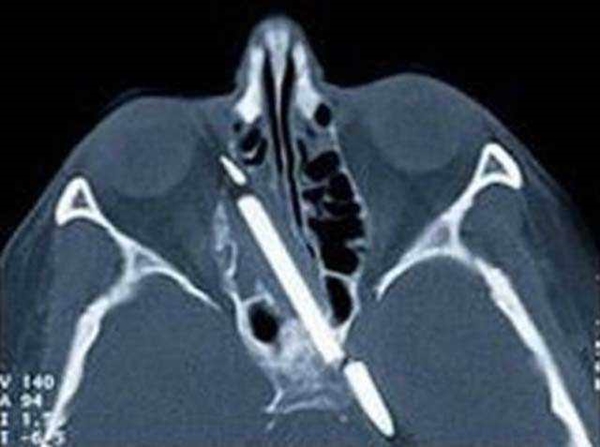

#9

Foto - 36 yıl sonra midesinden kardeşi çıktı!

Kafada bir kalem - Almanya'da bir kadın, 50 yıl boyunca kafasının içinde bir kalemle gezdi. 4 yaşındayken bir kaza geçirmiş, elinde kalemle yürürken ayağı kayıp düşmüştü. "kalem derimin içinden geçti ve kafamın içinde yok oldu" diyen kadın, pek çok kez operasyon geçirdi. başta doktorlar kalemin beyne yakın olması yüzünden ameliyat yapmaktan kaçındılar. Daha sonra bir kaç kez ameliyat olan kadının kafasındaki kalemin büyük bölümü çıkarıldı. Ancak kalemin ucu çıkarılamadı, çünkü beyin dokusuyla hemen hemen birleşmişti.